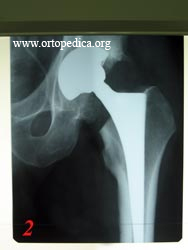

2. - Больной К. Состояние после эндопротезирования левого тазобедренного сустава протезом модели Zimmer Trilogy-Versys бесцементной(механической ) фиксации